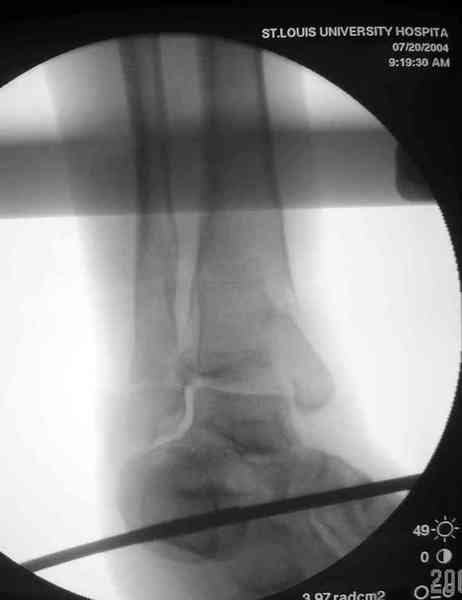

Добавлены КТ снимки. Прошу прощения за качество.

С уважением, Коваленко А.Н.

Снова приветствую вас, коллеги. К моменту вступления в обсуждение аксакалов, операция была, увы, выполнена(31.10.07.) Начали с доступа к наружной лодыжке, произвели ее фиксацию спицами, развернули кусок заднего края, наложили дистрактор, затем произвели дистракцию, фиксацию спицами дистального эпиметафиза б/бк,Рентгено-контроль. синтез наружной лодыжки 1/3пластиной. из двух коротких разрезов сформирован канал под медиальную тибиальную пластину LCP. Края ран ушиты без натяжения. Прочувствовать жесткость фиксации винтами с угловой стабильностью не удалось, поэтому дистрактор оставлен на энное время.

На представленных R-снимках не окончательный вид после остеосинтеза. Дистальная опора давила на стопу, пришлось ее сместить проксимально, в рез-те чего, она закрыла щель сустава, последние снимки не информативны.